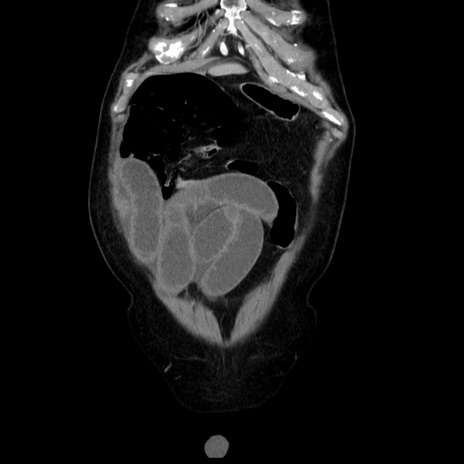

症例30(冠状断像)

【症例】80歳代男性

【主訴】臍周囲痛

【現病歴】約6時間前から臍下部痛が出現。次第に腹部膨隆・背部痛も生じてきたため来院。背部痛の場所は変化しない。

【身体所見】意識清明、BT 36.3℃、BP  131/87mmHg、P 87bpm、SpO2 100%(RA)、臍周囲自発痛・圧痛あり、反跳痛なし、自発痛部位に一致して板状硬あり、腹部膨隆、腸雑音減弱、CVA tenderness両側陰性。

【データ】WBC 19600、CRP 0.33